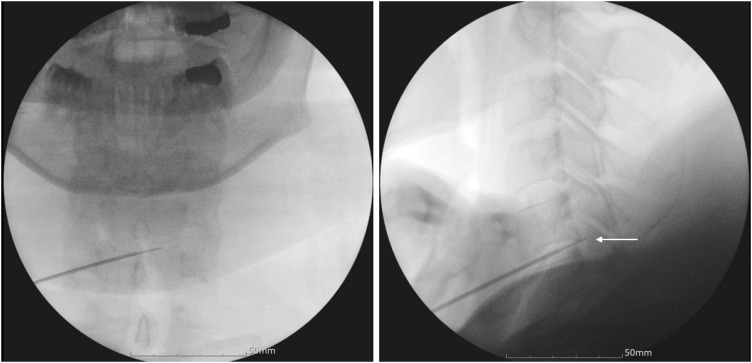

Intradiscal electrothermal therapy (IDET) is a minimally invasive procedure that alleviates chronic discogenic pain by delivering controlled heat to modify collagen and destroy pain-conducting nerve endings. While IDET offers a less invasive alternative to surgery, it carries risks such as nerve damage, infection, vertebral osteonecrosis, and, rarely, spinal cord injury. This report presents the case of a 36-year-old woman who developed left-sided hemiparesis following IDET for cervical disc herniation at the C5/6 level. Magnetic resonance imaging revealed cervical cord edema, and examination revealed neurological deficits, including reduced proprioception, motor strength, and senses of pain and temperature. Anterior cervical discectomy and fusion led to thermal injury on the left ventral spinal cord, and postoperative recovery resulted in significant neurological improvement, although some sensory deficits persisted. This case underscores the importance of appropriate patient selection and meticulous procedural technique to prevent severe complications, emphasizing the importance to reserve IDET for specific cases and to consider alternatives for more complex spinal conditions.